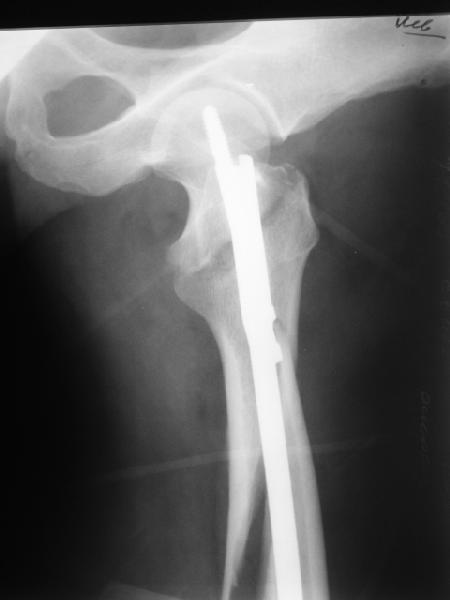

Второй случай тоже репозиция из малого доступа, больному 19 лет, множественные огнестрельные повреждениия конечностей, живота и черепа, правая конечность холодная, без пульсации. Ортопедический диагноз: огнестрельный перелом правого бедра. При срочной ангиографии повреждения сосудов не подтвердилось, конечность из-за ургентности состояния больного зафиксирована временным наружным фиксатором и больной оставлен на операционном столе для срочной лапаротомии хирургической службой.

Больной долго оставался нестабильным, только на 14 день удалось заменить на антеградный интромедуллярный штифт TFN (trochanteric femoral nail) SmithNephew. После неудачной попытки закрытой репозиции, несмотря на использование "joystick", проксимальный стержень от

наружного фиксатора, (перелом начал срастаться) репозицию провели из малого доступа, затем остальные этапы операции.

Случай был представлен из-за того, что больного оперировали после наружной фиксации и был риск инфекцирования через места проведения стержней (на снимках), прошло больше 3 месяцев, выписан из амбулаторной службы из-за отсутсвия надобности дальнейшего наблюдения.

Джолдас Кульджанов